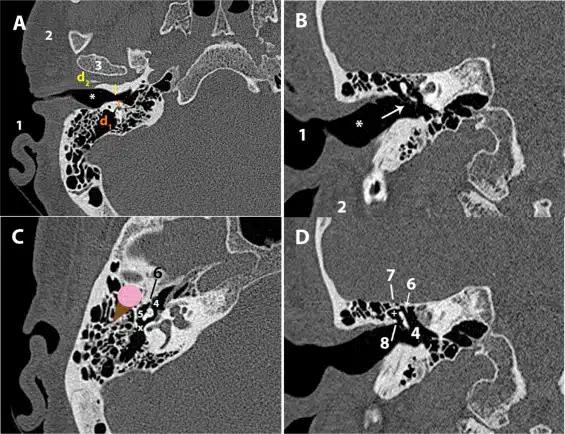

Lista de verificación de tomografía computarizada de hueso…

La tomografía computarizada del hueso temporal es una prueba de imagen fundamental para el diagnóstico y tratamiento de diversas entidades que afectan a esta compleja…